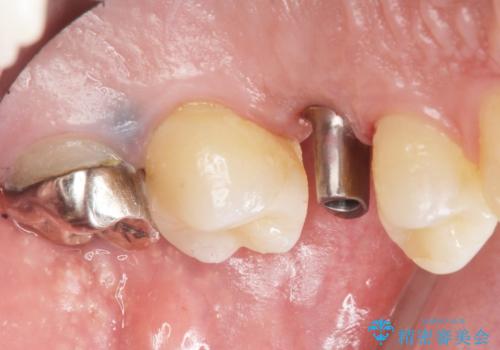

「違和感もなく、まるで自分の歯のようにしっかり咬めます!」と大変喜んで頂けました。

インプラントの種類:ストローマン BLT

被せ物の種類:オールセラミッククラウン スタンダード